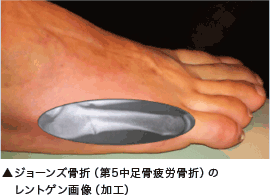

Jones fracture - ジョーンズ骨折

ジョーンズ骨折は、ランニングやジャンプ動作による過度の体重負荷が、長時間、足部アーチに繰り返し加わることで発生するオーバーユースに起因するスポーツ障害です。金属疲労(金属板の折り曲げ運動)と同様に、繰り返しのストレスが中足骨に加わって起こります。また一般的な骨折とは発生原因が異なり自覚症状が出にくいので、見過ごされることがあります。